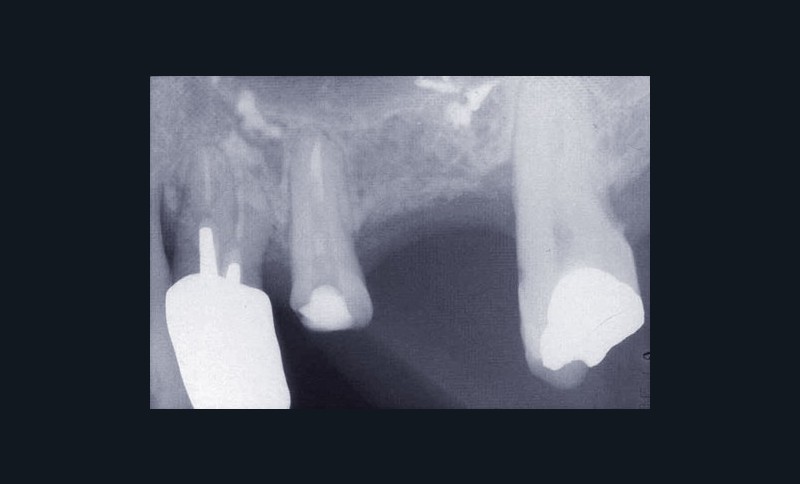

Une patiente âgée de 45 ans consulte à la fin des années 1990 avec une contention en échelle au maxillaire afin de soulager les mobilités des dents antérieures.

Les examens cliniques et radiographiques montrent une parodontite chronique généralisée (fig. 1a à m).

La patiente, en bonne santé, ne fume pas.

Nous décidons d’entreprendre une thérapeutique initiale parodontale classique dans tous les secteurs, y compris l’extraction de 24, un bridge de 45 à 48 avec 46 en pontique, un bridge complet de contention de 17 à 27 sur 11 piliers dentaires et une greffe épithélio-conjonctive sur 31. Cette dernière ne sera jamais réalisée. Le bridge maxillaire permettra de réduire le surplomb antérieur et d’améliorer le sourire de la patiente, ce qui constitue l’une de ses demandes.